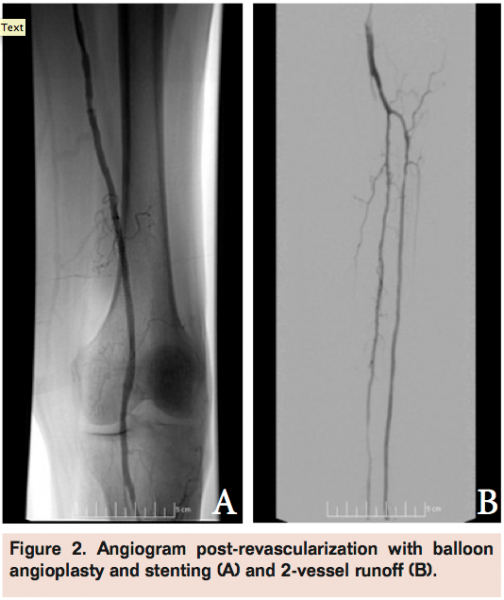

Angiogram of the left common femoral artery with runoff revealed distal left superficial femoral artery occlusion (Figure 1A) with reconstitution of the distal popliteal artery and 2-vessel runoff into the left foot via the anterior tibial and peroneal arteries (Figure 1B). Revascularization of the occlusion was performed using balloon angioplasty and stent placement (Figure 2A) with good angiographic result and runoff (Figure 2B). She had complete resolution of her claudication symptoms, but returned 1 year later with ulceration of the medial aspect of her left foot above the medial malleolus. Repeat angiogram revealed restenosis of the stent (Figure 3A) and re-occlusive disease of the distal popliteal artery stent extending into the anterior tibial artery (Figure 3B) requiring atherectomy and balloon angioplasty for successful revascularization (Figure 4). However, her ulceration progressed despite revascularization, prompting further evaluation of the etiology of her ulcer (Figure 5). A venous Doppler study of the left lower extremity revealed severe reflux of the left greater saphenous vein (Figure 6) with flow above baseline in the proximal, mid, and distal portions of up to 1.7 seconds. An incompetent perforating vein was also noted in the left calf 23 cm from the ankle and measured at 0.33 cm in diameter (Figure 7). She subsequently underwent radiofrequency ablation of the left greater saphenous vein followed by the left calf perforator with complete occlusion by ultrasound (Figure 8).